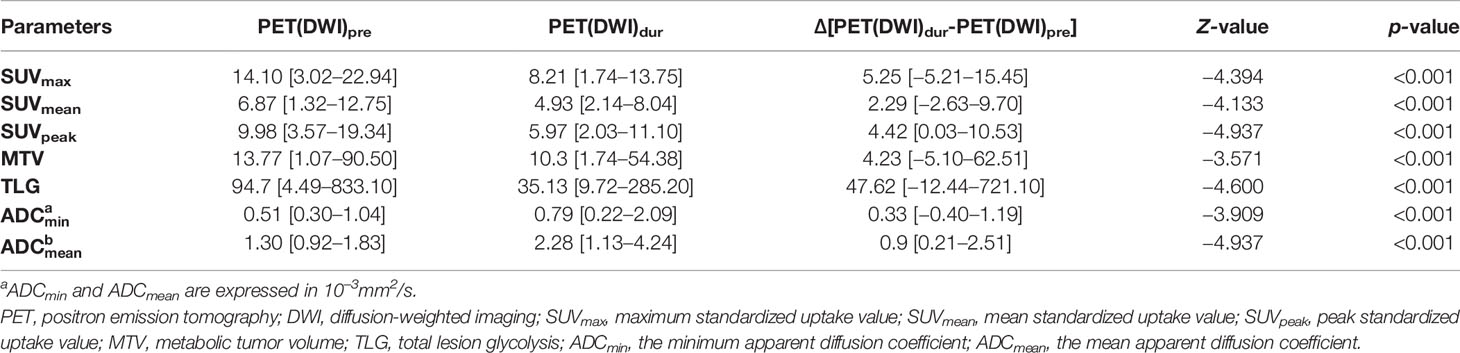

SUV and ADC Values

Table 2 summarizes the results of SUVs (SUVmax, SUVmean, and SUVpeak) and ADCs (ADCmean and ADCmin) performed before and during RT. The differences in SUVs (SUVmax, SUVmean, and SUVpeak), MTV, TLG, and ADCs (ADCmean and ADCmin) values as determined on 18F-FDG PET-CT and DW-MRI before and during RT were significant (both p < 0.001). A trend toward lower SUV and higher ADC was observed during the treatment process.

Associations of SUVs and ADCs With Clinical Prognostic Factors

Table 4 shows associations of SUVs and ADCs with clinical T-stage and longitudinal length of GTVs. The SUVs (SUVmax, SUVmean, and SUVpeak), MTV, and TLG pre-RT and its relative changes between pre-RT and after 15 fractions of RT were significantly higher in stages T3–4 than in stage T2 and in the group with a longitudinal length of GTVs ≥4 cm than <4 cm (p = 0.000−0.041). The ADCmin dur-RT and its relative changes between pre-RT and after 15 fractions of RT were significantly lower in the group with a longitudinal length of GTVs ≥4 cm than <4 cm, but these were not significantly associated with clinical T-stage (Table 4).